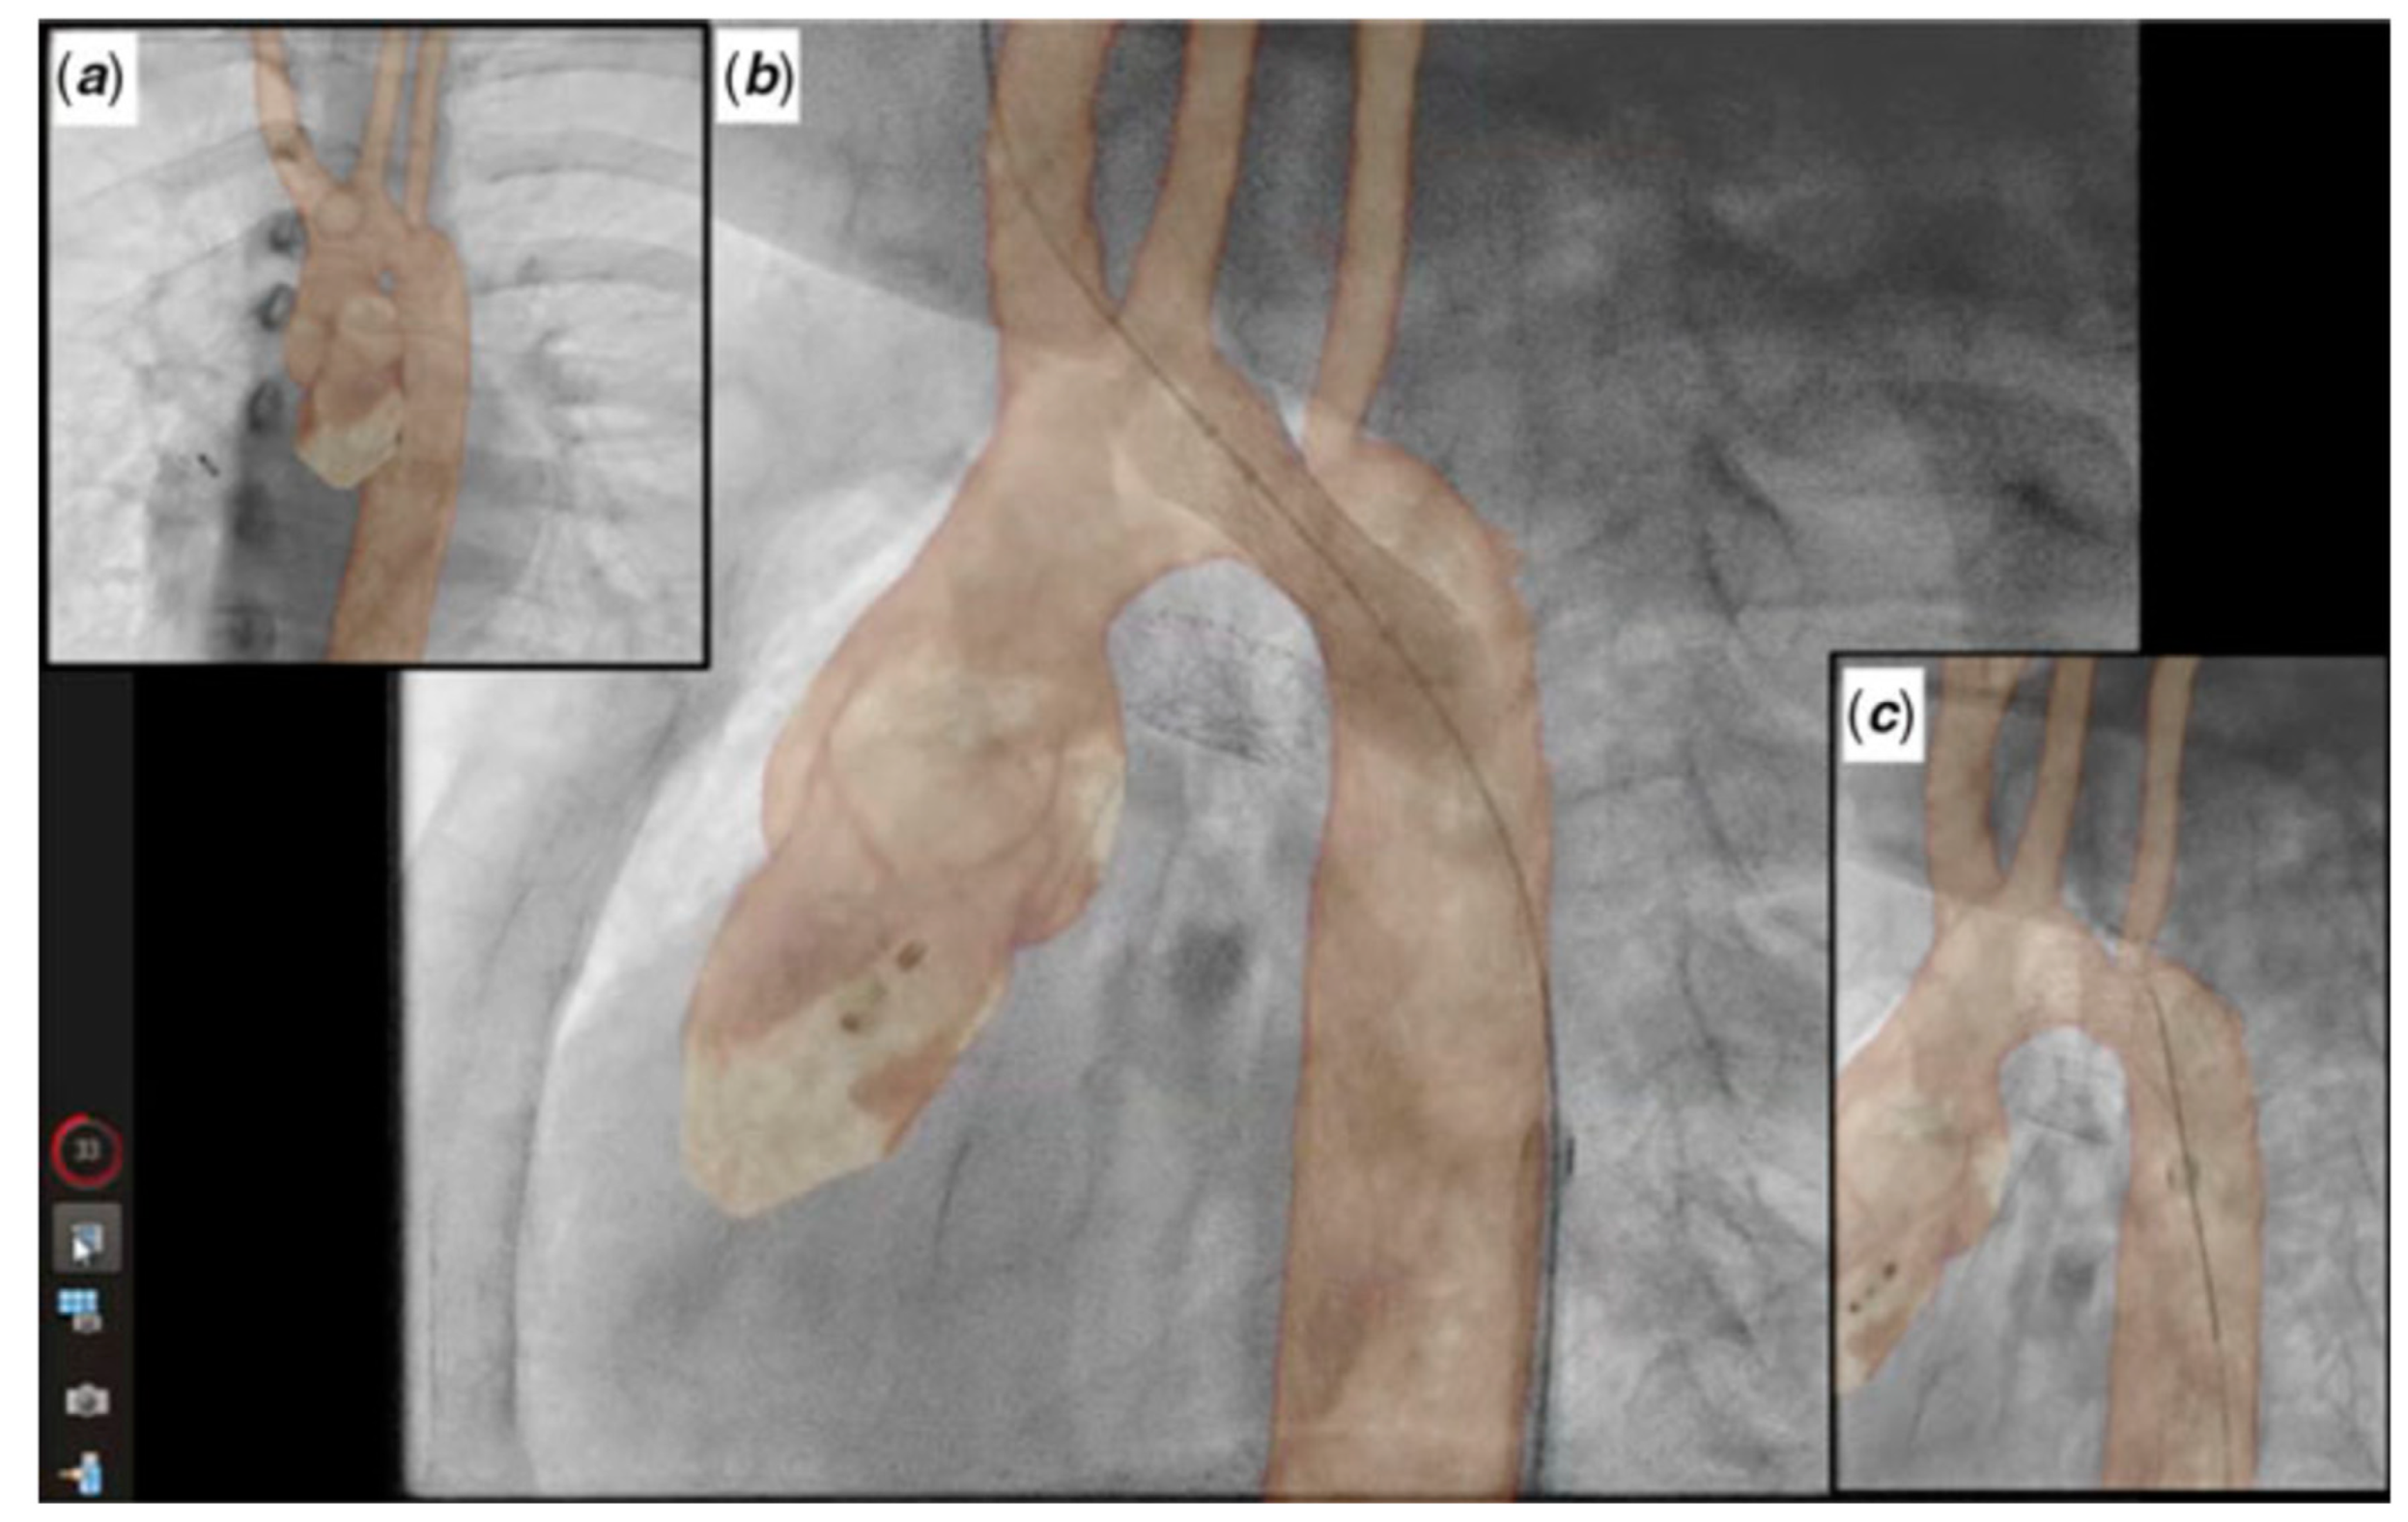

2.4. Cross-Sectional Overlay Fusion in the Catheterization Lab

2.5. Coronary Artery Assessment in CHD